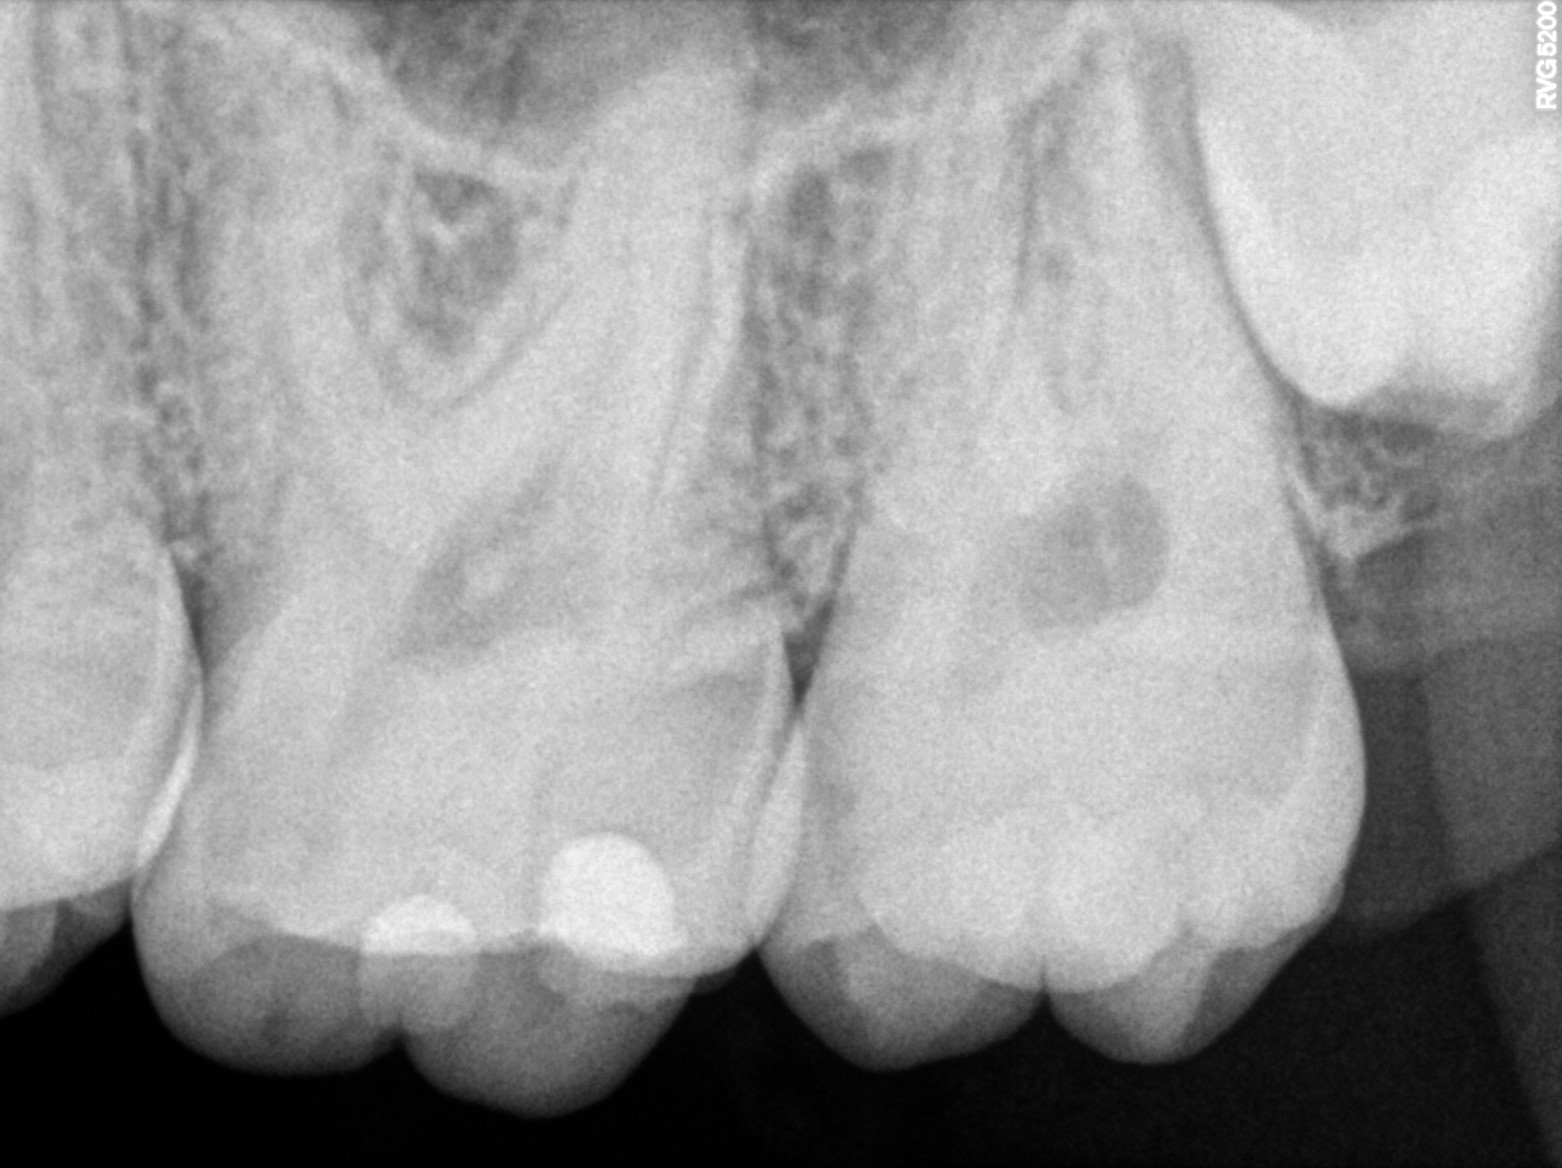

Dental Radiographs FHIR: DocumentReference · LOINC 24641-7

R64.jpg

24641-7